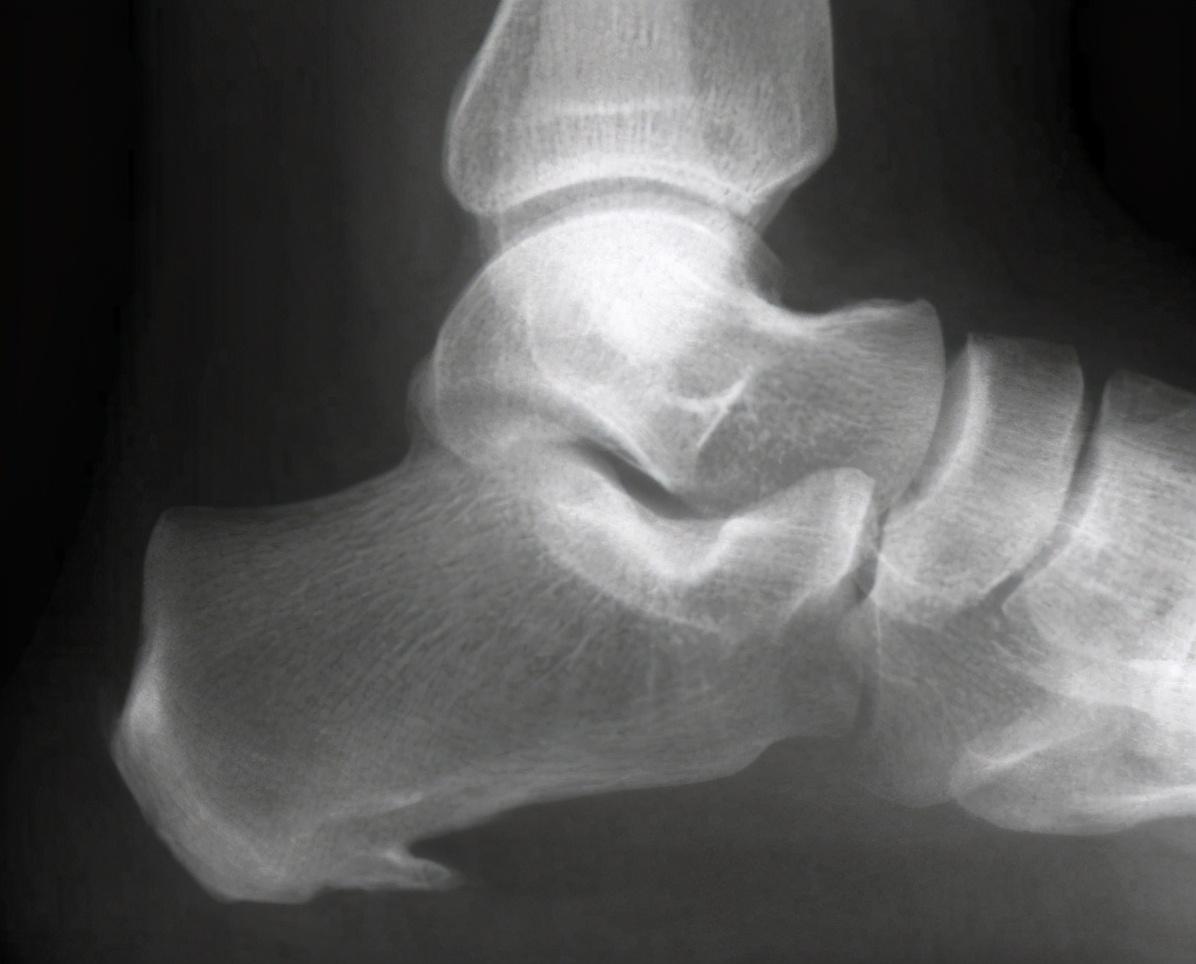

想要控制好血糖 , 最主要的还是管住嘴 , 迈开腿 。 不要相信那些偏方 。二、类风湿关节炎 。在临床中 , 类风湿关节炎的患者也是很常见的 , 我们国家的发病率是0.42% , 也就是说总共发生的不是关节炎的人群有500万之多 。

这种疾病最大的表现就是双手、双腕或者双足 , 这种关节出现肿胀和疼痛 。 经常是早晨起来感觉关节僵硬 , 下地活动之后感觉轻松很多 。

随着病情的进展 , 关节破坏也越来越严重 , 严重的患者会出现关节畸形 。 严重地影响正常的关节活动 。

严格意义上讲 , 类风湿关节炎是一种慢性关节炎症 , 但是需要注意 , 虽然目前可以考虑应用的药物很多 , 也有一些患者可以有很好的治疗效果 , 但是内风湿关节炎仍然是一种不可能根治的疾病 。